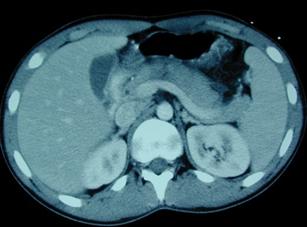

Rinichiul drept Rinichiul

drept

Extravazarea substantei de contrast Defect de

umplere - pol superior